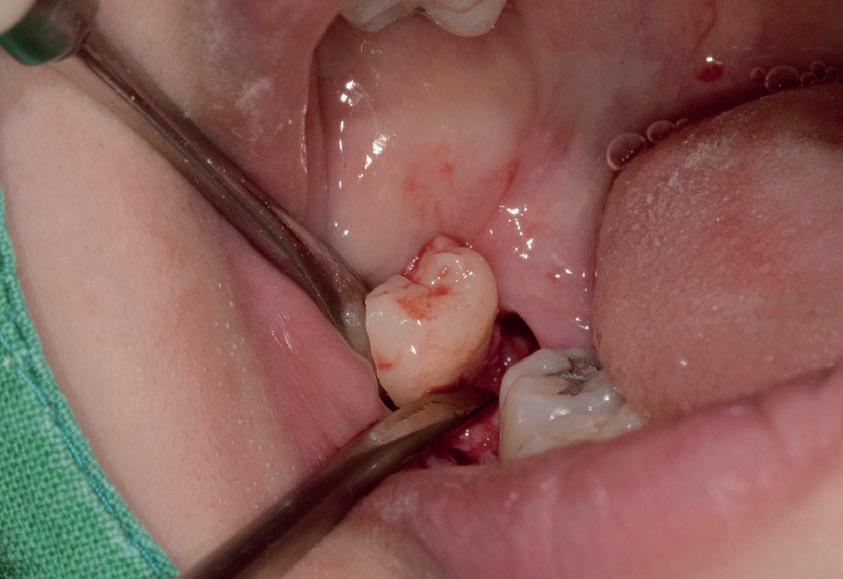

L’estrazione di un dente del giudizio incluso orizzontalmente, sfruttando questa tecnica con il manipolo dritto, richiede un’ulteriore rimozione di struttura dentale e di osso. Figg. 180-183

Per questo motivo, il lembo deve essere esteso fino al primo molare e bisogna avere una visione del sito chirurgico adeguata. Più il dente è inclinato orizzontalmente più la rimozione di osso vestibolare è necessaria.

Solitamente viene utilizzata una fresa a fessura dritta da manipolo per sezionare le radici, ma è preferibile usare una fresa rotonda laddove c’è la necessità di rimuovere l’osso alveolare attorno alla corona, come mostrato in fotografia. Figg. 184-187

In questo caso la separazione del periostio e la rimozione di osso vestibolare è quasi inevitabile per estrarre il #38.

Figg. 180-187 - Un caso di un’estrazione di un dente del giudizio, utilizzando il manipolo dritto. Fig. 180 Fig. 181 Fig. 182 Fig. 183 Fig. 184 Fig. 185 Fig. 186 Fig. 187